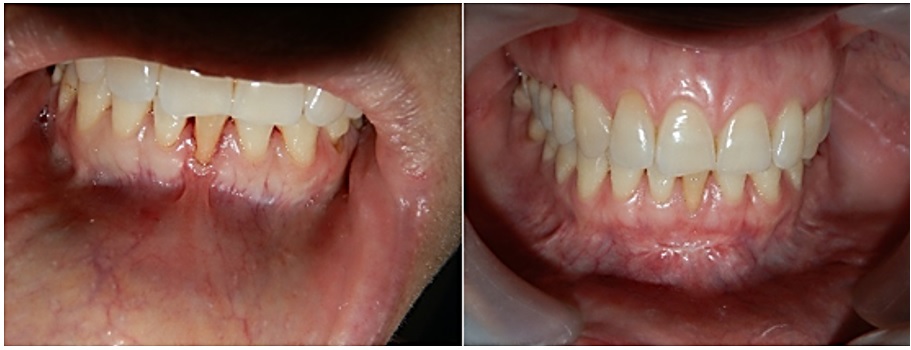

Un hombre de 21 años de edad estuvo en consulta por presentar seudoanodoncia del canino inferior izquierdo (diente 33), mal posición de los incisivos anteriores inferiores, periodonto sano con pérdida de inserción en los incisivos centrales inferiores izquierdo y derecho (dientes 31 y 41, respectivamente) e inserción anómala del frenillo labial inferior. Comentó que se sentía inconforme por la ausencia de su canino inferior izquierdo. En el examen clínico se observó un vestíbulo poco profundo, poca resiliencia, frenillo labial inferior casi imperceptible y recesiones en las zonas anteriores de los dientes 31 y 41. Al sondeo no se encontraron bolsas periodontales o evidencia de encía insertada insuficiente (figura 4). Se clasificó como recesión clase I, según Miller, y se evaluó la necesidad de implementar terapia etiotrópica periodontal por medio de raspado, alisado radicular y profilaxis antes de cualquier consideración quirúrgica. Se decidió llevar a cabo manejo quirúrgico y ortodóntico para corregir la retracción gingival y controlar el riesgo de complicaciones. Se buscaba liberar el diente 33 para luego, con ayuda de un botón ortodóntico y colocación de aparatología fija, retraerlo.

Se presentó a consulta una mujer de 30 años de edad con gingivitis marginal generalizada, pérdida de inserción localizada en el incisivo central inferior derecho (diente 41) e inserción anómala del frenillo labial inferior. La paciente no estaba conforme con la apariencia de su encía en la parte anteroinferior. En el examen se observó un vestíbulo poco profundo, poca resiliencia, frenillo labial inferior casi imperceptible, eritema en la encía marginal y recesión marcada en el diente 41. Al sondeo no se encontraron bolsas periodontales o evidencia de encía insertada insuficiente (figura 5). Se clasificó como recesión clase II, según Miller, y se evaluó la necesidad de implementar una terapia etiotrópica periodontal a través de raspado, alisado radicular y profilaxis antes de cualquier consideración quirúrgica. Se decidió realizar cirugía para corregir la retracción gingival y controlar factores de riesgo.